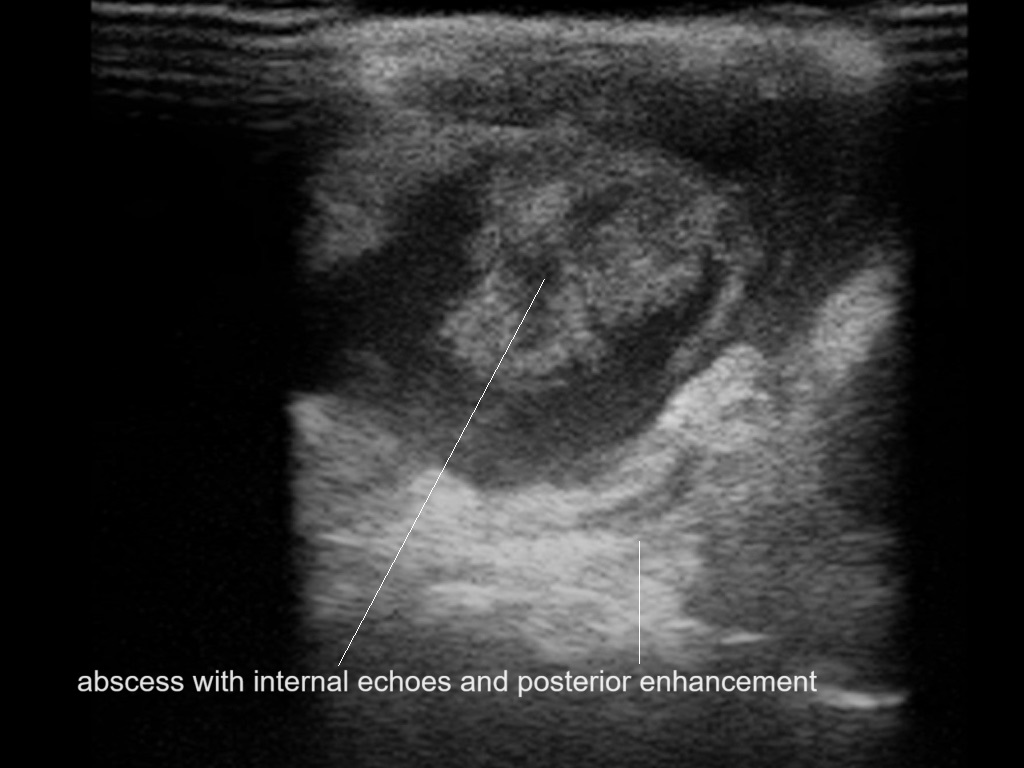

With ultrasound signs of inflammation can be visualized. Edema can be seen as a hyperechoic appearance of the subcutaneous fat, sometimes separated by hypoechoic fluid filled area’s, known as cobblestone appearance. Increased vascularization (hypervascularity) can be seen on colour Doppler. An abscess will appear as a fluid collection appearing as an irregular hypoechoic area with heterogeneous internal echoes and a thickened wall. Posterior acoustic enhancement can be present, and there is vascularity around but not within the mass. Under ultrasound guidance, abscesses can be managed by needle aspirations (18G) under antibiotic cover.